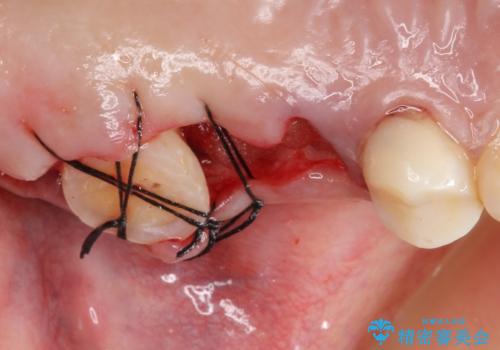

奥歯3本(左上567)はう蝕が深く保存不可能な状態であったため、やむなく抜歯しました。

使っていない親知らず(左上8)を左上7抜歯窩に移植し、支台歯としてブリッジによる補綴治療を行いました。